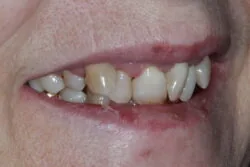

Presenting condition

A comprehensive periodontal examination revealed widespread pocketing and clinical signs of mobility in the anterior region. The upper central and lateral incisors were the most severely affected, and they showed persistent instability despite improvements elsewhere. Generalised recession and attachment loss were confirmed, with periodontal charting from September 2023 and follow-up data in November 2023 demonstrating the extent of disease and its subsequent management.

Pre-treatment images